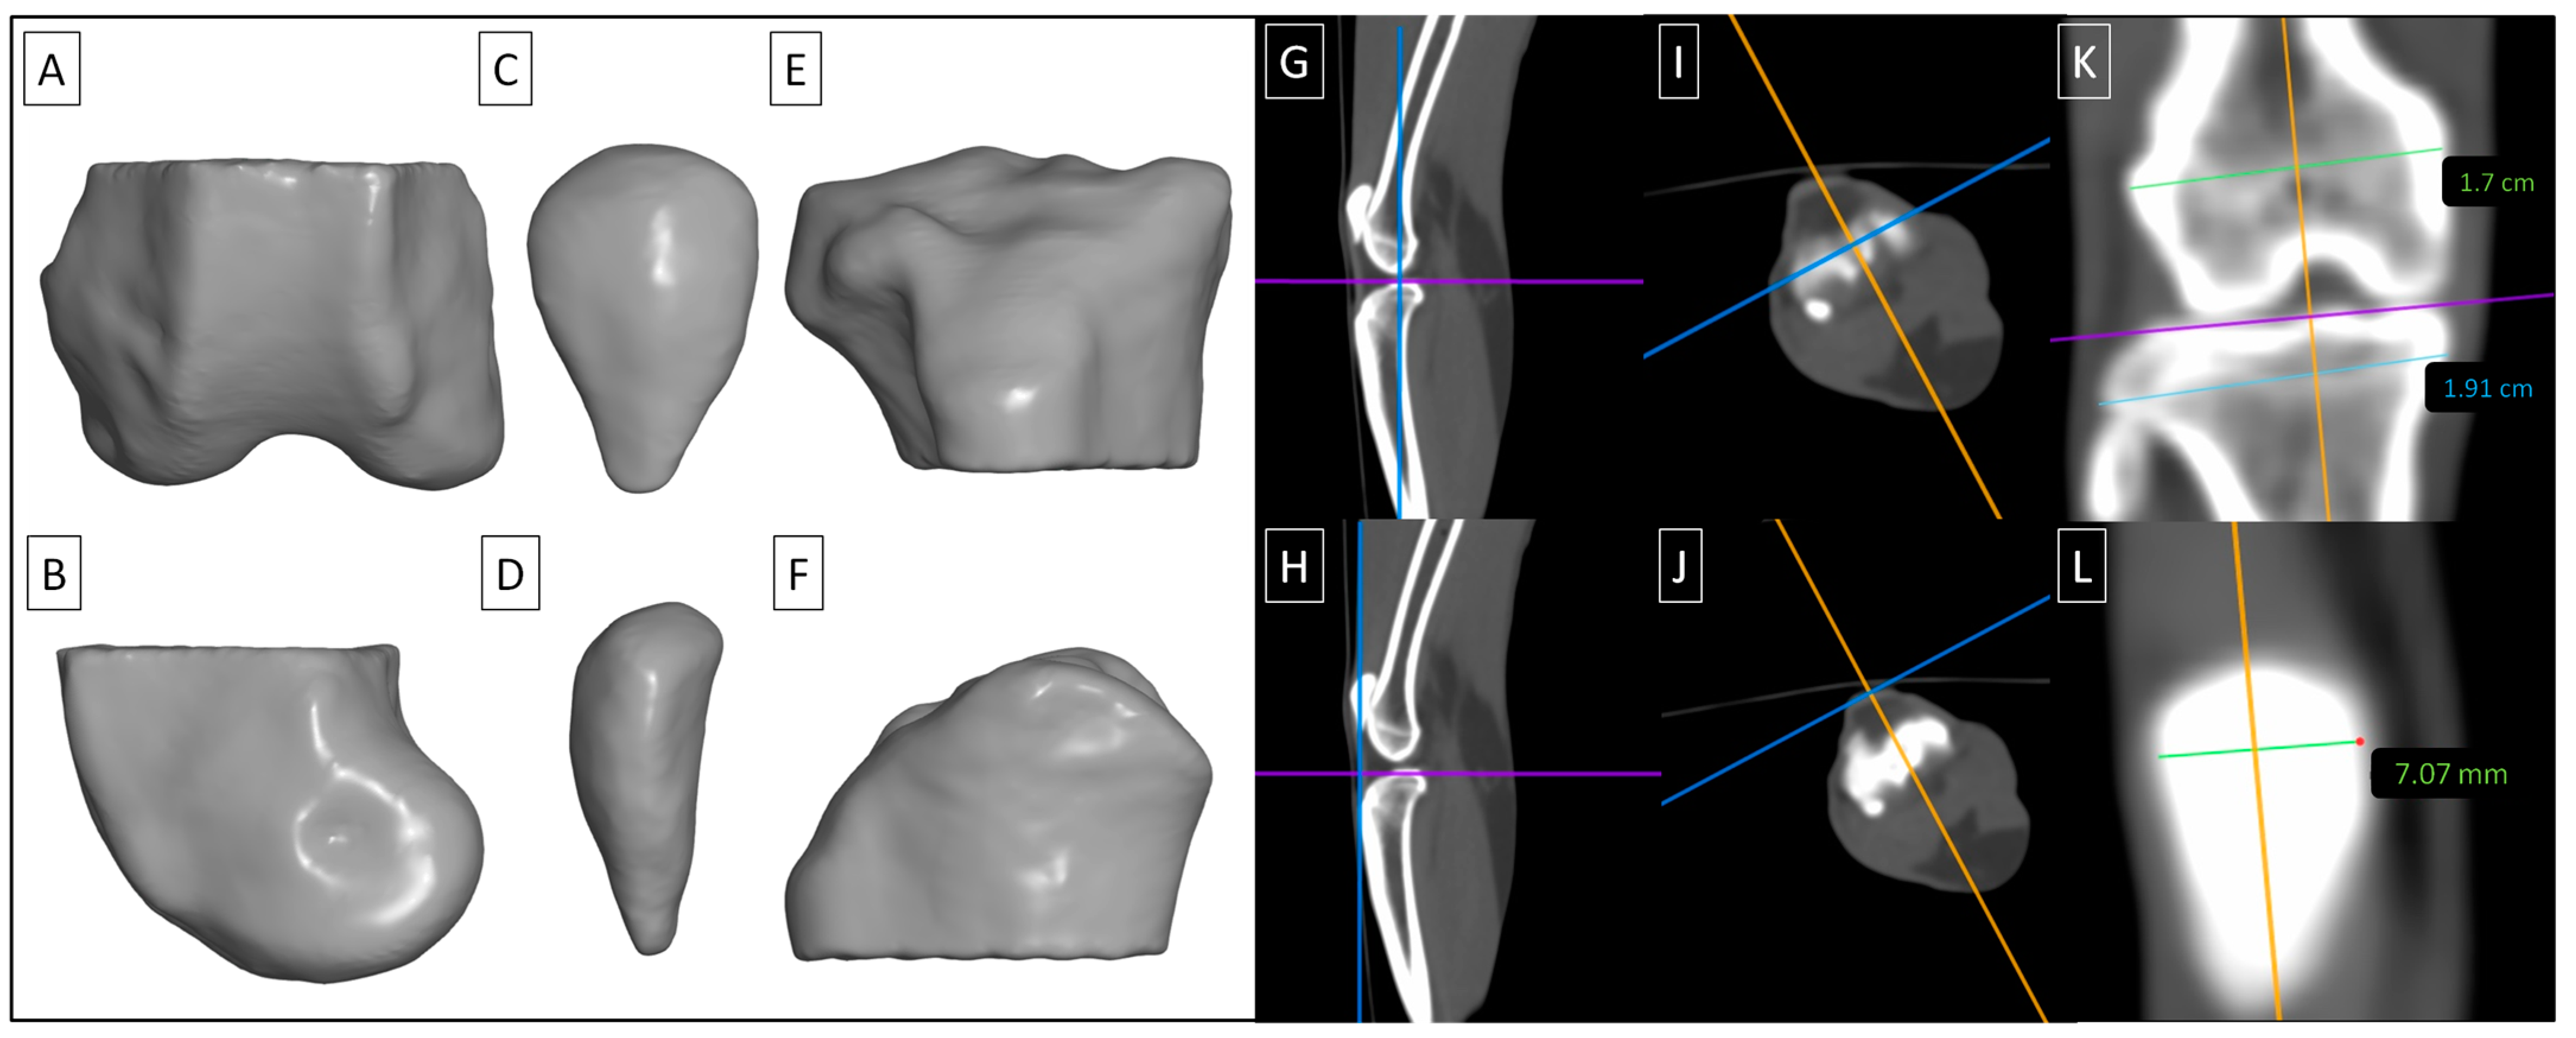

Three regions of interest (ROIs) were semi-automatically segmented on each limb following ranges suggested by Boyd et al. [45]. ROI 1 represented the distal epiphysis of the femur (Figure 3A,B), ROI 2 represented the patella (Figure 3C,D), and ROI 3 represented the proximal epiphysis of the tibia (Figure 3E,F). Segmentation was conducted using Materialises Interactive Medical Image Control System (MIMICS) software version 14.0 (Materialise HQ, Leuven, Belgium). The tomograms in DICOM format were imported into MIMICS software, and gray level mapping was set between −1023 HU and 3056 HU. Tissues with a density ≥450 HU [45] were semi-automatically annotated and then corrected manually to separate the representative ROIs. For each segmented ROI, the vBMD values were extracted in HU.

Figure 3.

Three regions of interest (ROIs) were segmented in each knee joint, including the distal epiphysis of the femur (ROI 1) (A,B), the patella (ROI 2) (C,D), and the proximal epiphysis of the tibia (ROI 3) (E,F). ROIs are displayed in a dorsocaudal view (A,C,E) and mediolateral view (B,D,F). The tomograms were positioned in the sagittal (G,H), transverse (I,J), and coronal (K,L) planes for measuring the width of the distal femur (G,I,K), patella (H,J,L), and proximal tibia (G,I,K).

Then, the tomograms were displayed using a bone window set at a level of +350 and a width of 2000 using Osirix MD software version 12.0 (Pixmeo SARL, Bernex, Switzerland). This setting was used to measure the width of the desired anatomical structures, with the knee joints always positioned in the same manner in the sagittal (Figure 3G,H), transverse (Figure 3I,J), and coronal (Figure 3K,L) planes. All measurements were carried out on images in the coronal plane. The width of the distal epiphysis of the femur (distal femur) was measured as the longest distance between the lateral and medial epicondyles, parallel to the joint space (Figure 3G,I,K). The width of the patella was measured in the widest point (Figure 3H,J,L). The width of the proximal epiphysis of the tibia (proximal tibia) was measured as the longest distance between the lateral and medial condyles, parallel to the joint space (Figure 3G,I,K).